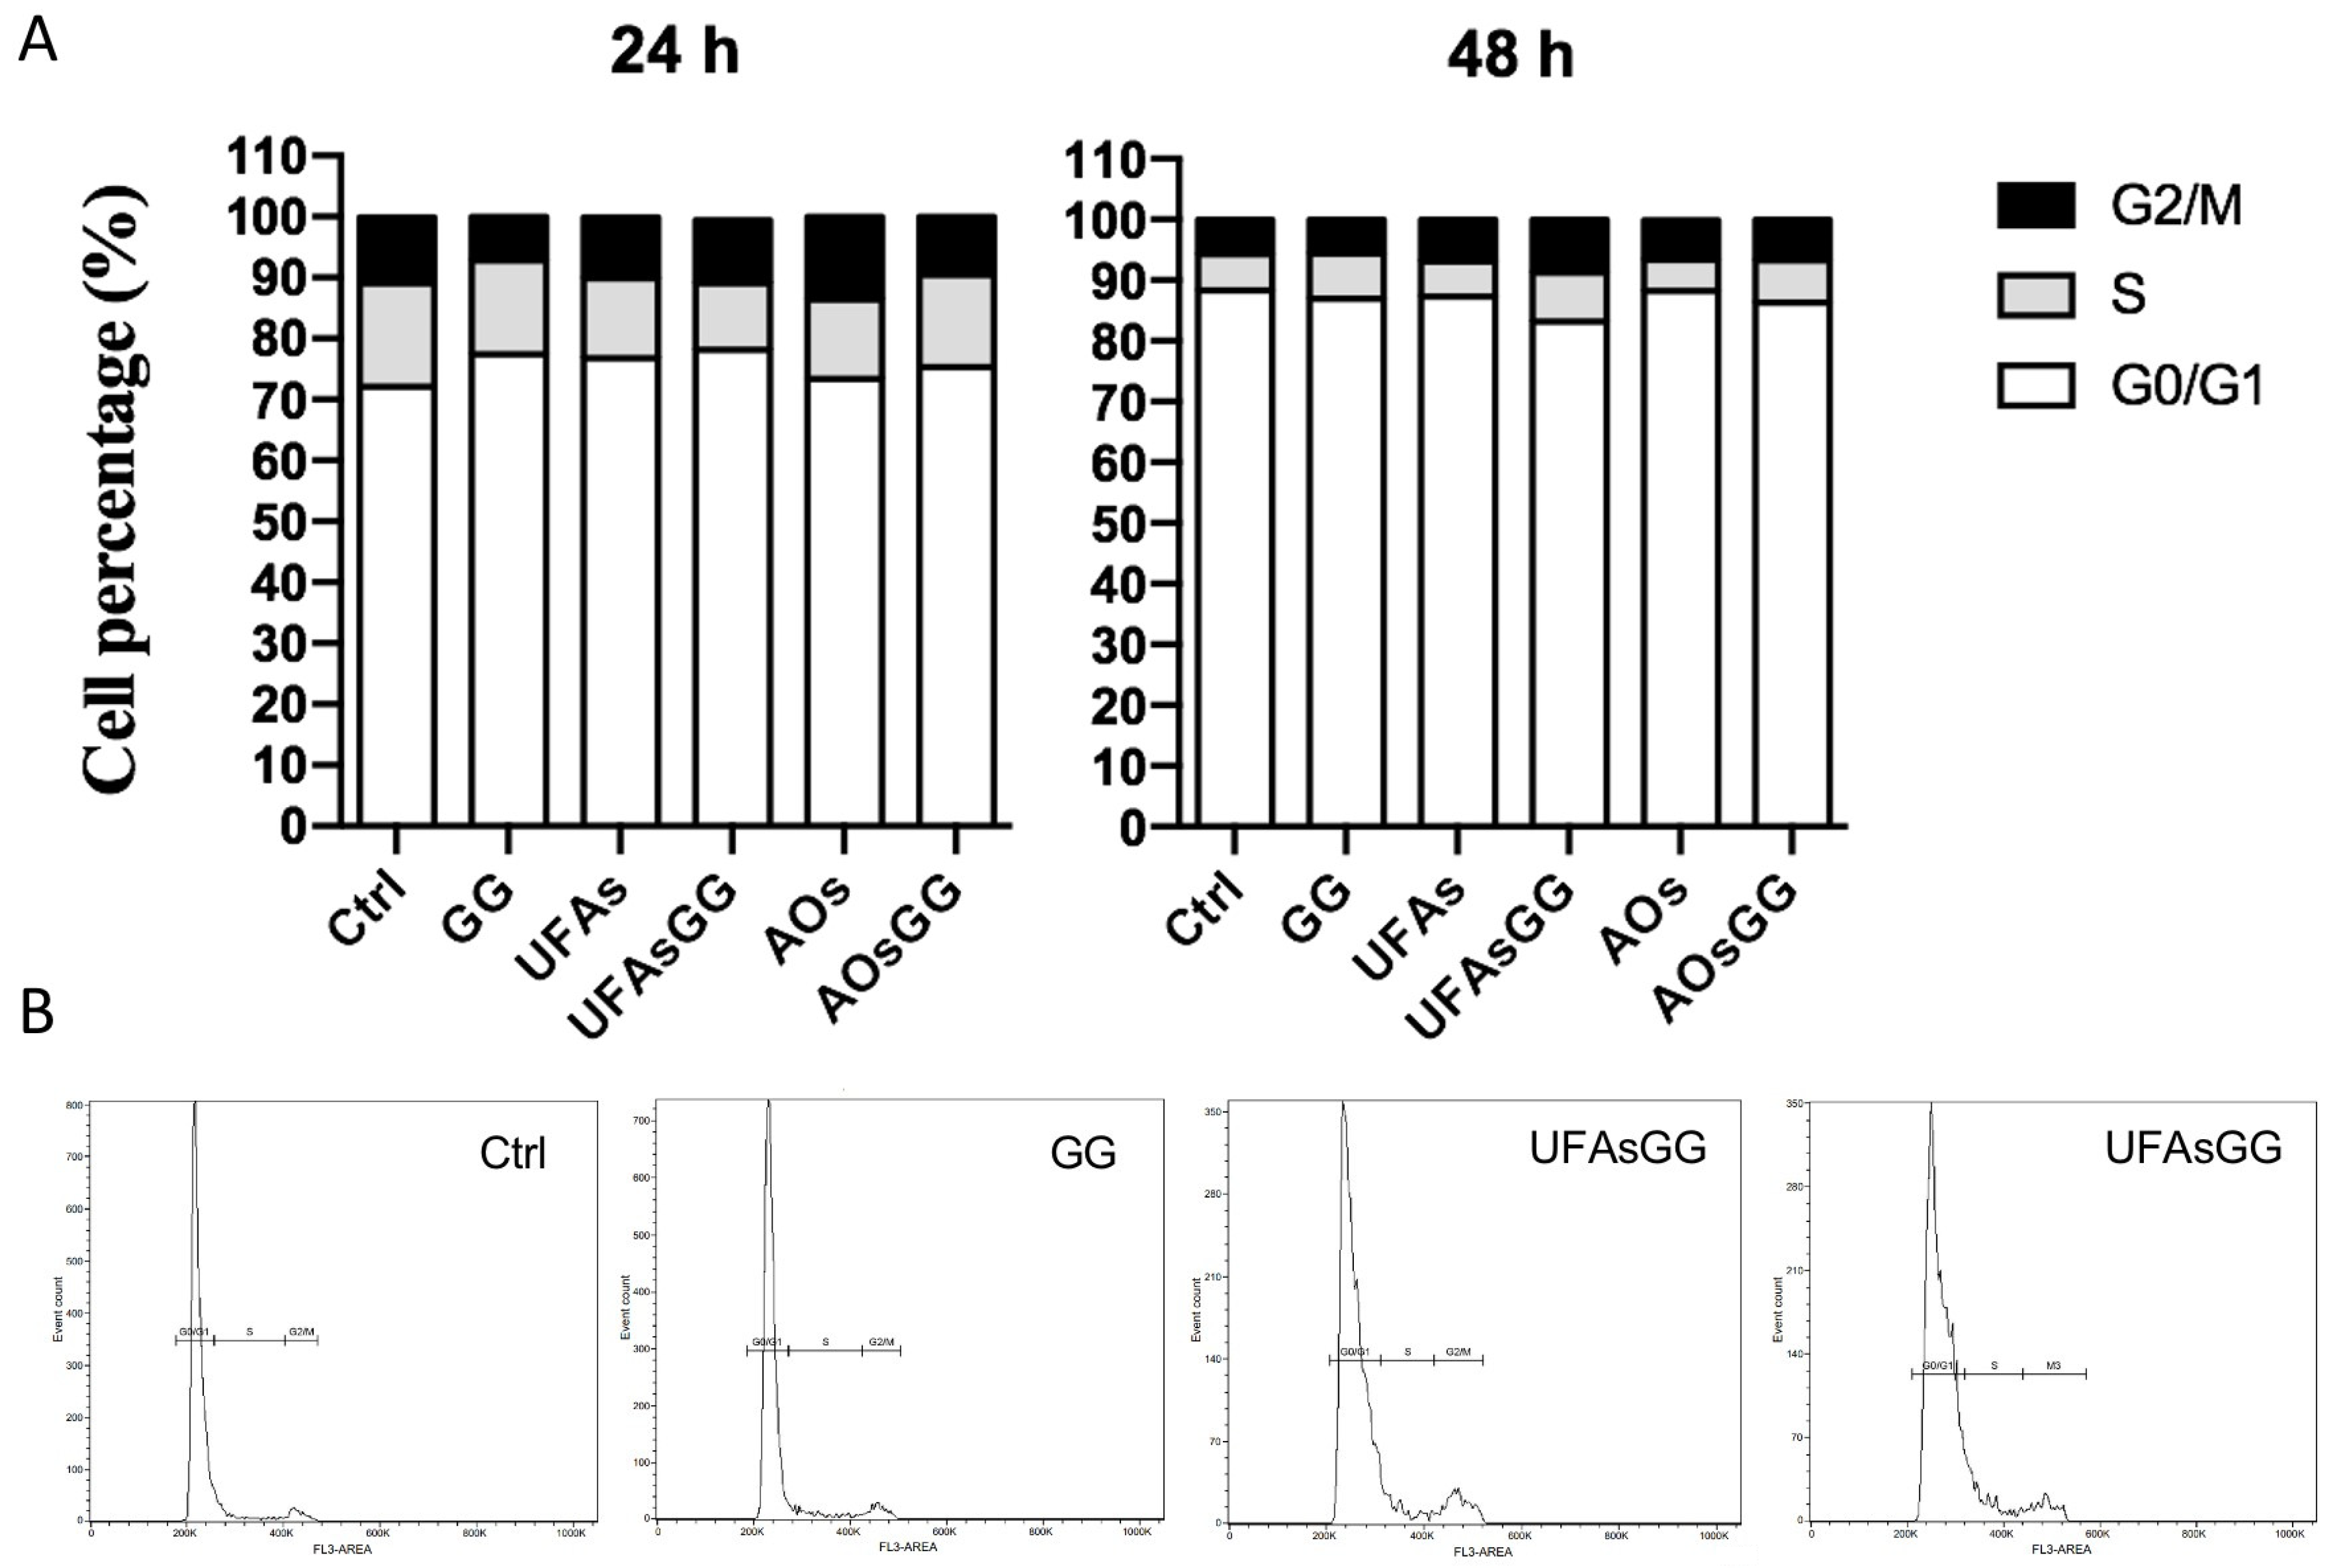

2.7. Cell Cycle Evaluation by Flow Cytometry

3.6.6. Cell Cycle Evaluation by Flow Cytometry